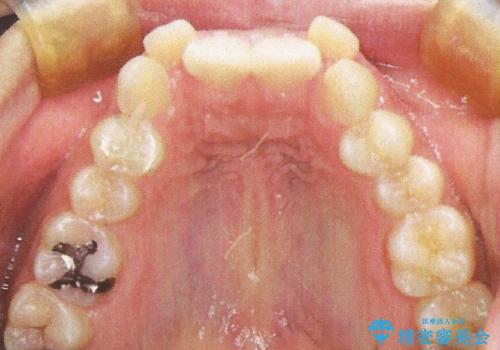

- 前歯のガタガタを主訴に来院されました。

前歯の重度のガタガタで、八重歯もある状態でした。

また右下の乳歯が残っており、永久歯が1本足りませんでした。

上顎両側と左下の前から4番目の歯と、右下の乳歯を抜歯して矯正することとなりました。